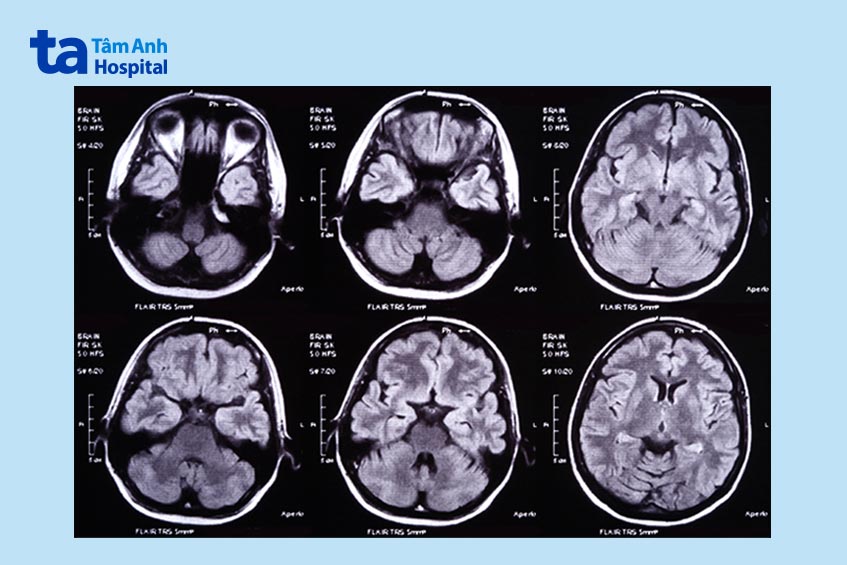

Bác sĩ sẽ xem xét tiền sử bệnh lý, lịch sử xảy ra chấn thương, các triệu chứng và chỉ định cho người bệnh thực hiện những kỹ thuật chẩn đoán hình ảnh cận lâm sàng nhất định, có thể bao gồm: